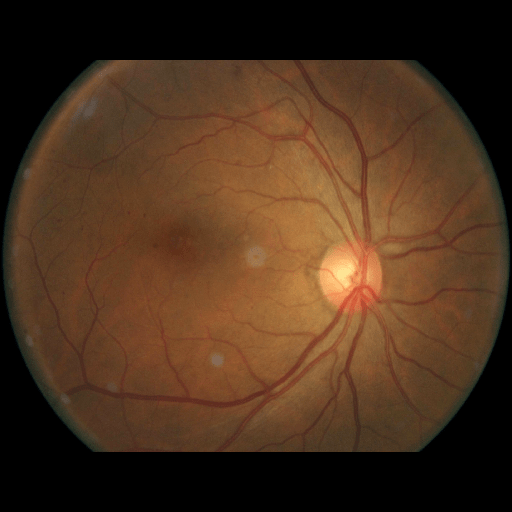

We conducted a case study on diagnosing diabetic retinopathy with ensembles of DL models. For benchmarking the performance of our ensemble-based solutions under the scheme described in Sec.3.3, we used two popular collections of diabetic retinopathy image data, the Kaggle Diabetic Retinopathy dataset [22] (hereafter referred to as “Kaggle-DR”) and the Messidor-2 dataset [23], each respectively consisting of and high resolution images. Diabetic retinopathy is graded into five SLs, as displayed in Figure 2. Following the problem setup used in previous papers [24], we trained models to distinguish the referable (SL2-4) cases from the non-referable ones (SL0 & SL1) (see Section B.1 for more detailed descriptions). We also tested our trained ensemble models on two o.o.d. image datasets (ImageNet [25] and CIFAR-10 [26]) to examine their capabilities of identifying o.o.d. inputs (see Section B in the supplementary materials).

The Kaggle-DR dataset comprises high resolution images. The presence of diabetic retinopathy is rated into five different SLs: no-DR (SL0), mild (SL1), moderate (SL2), severe (SL3), and proliferate (SL4), as illustrated in Figure 2. We divided the Kaggle-DR dataset into a development set and a test set, which respectively consisted of and images. The data in the development set were used to train and validate our Deep Learning (DL) models. The Messidor-2 dataset [38] that consisted of images was also used in our experiment as an additional dataset to test the true generalization performance of the models trained on the Kaggle-DR dataset. Images in Messidor-2 dataset were graded into the five SLs as in the Kaggle-DR dataset. Figure S.1 provides an illustration of the datasets used in our experiments.